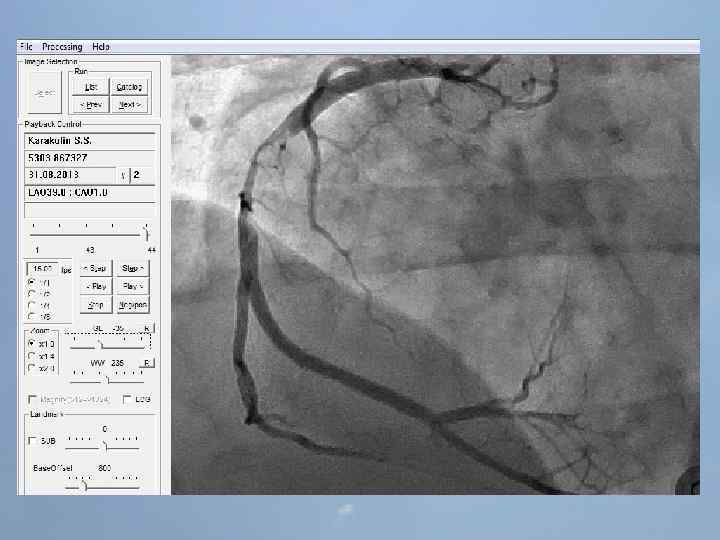

Пациент Б. , 54 года 29. 08. 13 около 10: 00, находясь на рабочем месте, почувствовал боль в груди. После 2 -ух приемов нитроспрея боль не уменьшилась, вызвал СМП. В 10: 20 первой бригадой СМП зафиксирован подъем ST на ЭКГ, начата ТЛТ, вызвана реанимационная бригада. В 10: 50 на месте вызова в присутствии реаниматолога у пациента развивается остановка кровообращения по типу фибрилляции желудочков. Выполнялась СЛР с непрямым массажем сердца, ИВЛ мехом, дефибрилляцией. В течение транспортировки фибрилляция рецидивировала еще 4 раза. Пациент доставлен в ООКБ в 11: 30, минуя приемное отделение госпитализирован в ОРИТ ОИМ.